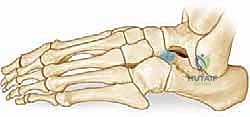

- الشق الجراحي: يُجري الدكتور هطيف شقاً جراحياً دقيقاً (شق أولييه - Ollier's incision) على الجانب الخارجي للقدم فوق منطقة الالتصاق مباشرة، مع الحرص الشديد على حماية الأعصاب والأوتار المحيطة باستخدام تقنيات الجراحة الميكروسكوبية.

- تحديد وعزل الالتصاق: يتم إبعاد العضلات والأوتار بلطف للوصول إلى الجسر العظمي الذي يربط بين العقب والعظم الزورقي. يتم تحديد حواف الالتصاق بدقة متناهية.

- الاستئصال العظمي الدقيق: باستخدام أدوات جراحية دقيقة (Osteotomes) ومناشير عظمية متطورة، يقوم الدكتور هطيف بإزالة الجسر العظمي بالكامل. يتم استئصال الالتصاق على شكل "مستطيل" لضمان إزالة مساحة كافية تمنع احتكاك العظمتين مجدداً وتسمح بحركة حرة.